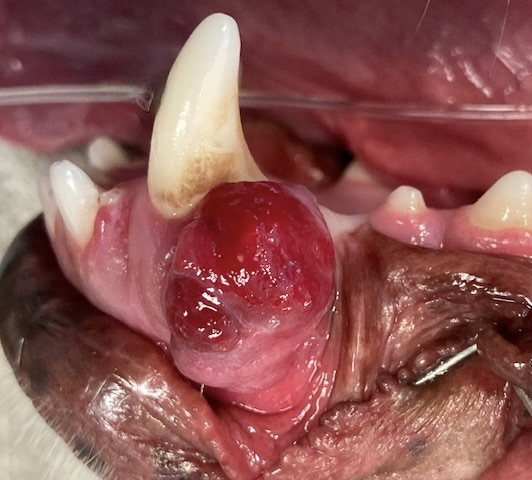

Oral Tumors

Oral growths or masses can develop in cats and dogs. These tumors (any abnormal growth) can be malignant/cancerous, or benign/noncancerous. Some cancerous tumors can look benign, and some benign tumors can look cancerous.

Therefore, it is key to have a veterinarian examine these growths. Your veterinarian may refer your pet to a board-certified dentist for evaluation and treatment.

Imaging such as dental radiographs (x-rays) or advanced imaging such as a CT or CBCT may be needed. A biopsy is very important to determine what type of tumor it is (cancerous or noncancerous) and how it will behave (invasive or non-invasive, slow or fast spreading, etc.).